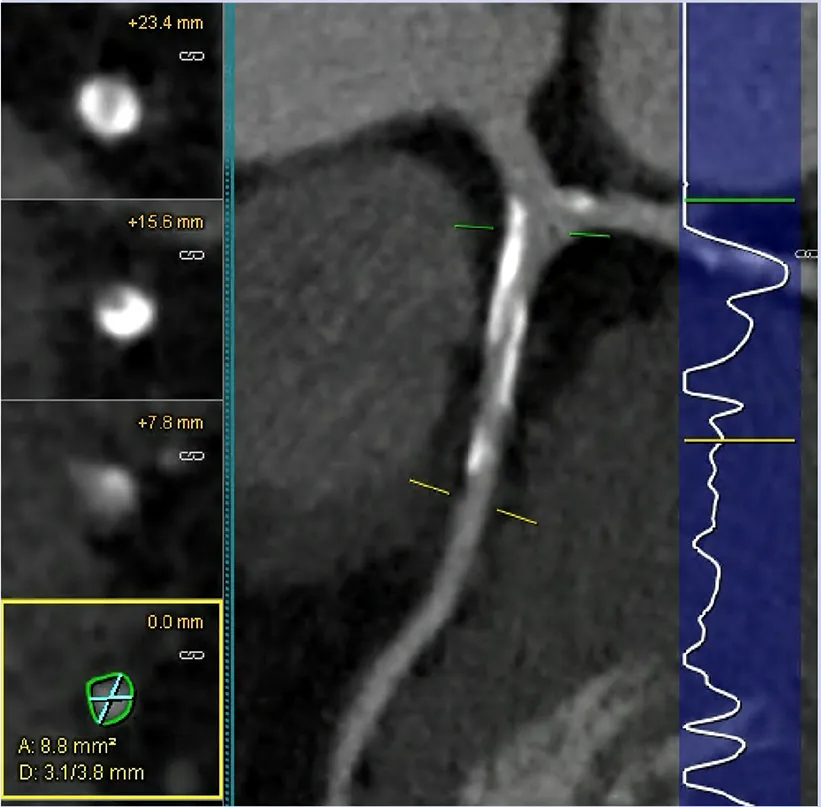

An important CCTA feature relevant for application in clinical trials is the ability to analyse and to quantify specific elements of coronary plaque. Through the use of Hounsfield Unit assessments, CT imaging can detect plaques at various stages of atherosclerosis including calcified plaque, fibrous and fibrofatty plaque, and earlier and more metabolically active lipid-rich plaques. Additional data can include markers such as pericoronary and epicardial fat. Several high-risk plaque (HRP) features are associated with higher rates of clinical events (23), such as low-attenuation plaque, spotty calcification, positive remodelling, and the so-called “napkin ring sign”. This is particularly valuable if the imaging endpoint is used as an enrichment biomarker for MACE-based studies, or as a pharmacodynamic response biomarker to assess the effect of therapy. Volumetric quantitation and differentiation of plaque subtypes are available with intra-coronary imaging modalities of intravascular ultrasound and optical coherence tomography, but the invasive nature of needing to cannulate and image from within a coronary artery limits wide applicability. These interventional techniques are also limited to larger more proximal vessels and can be difficult to pass through severely stenotic lesions. Fortunately, accuracy of CCTA to analyse plaque morphology compares favourably with these invasive techniques (24–26). However, for purposes of measuring potential benefits of new therapeutic interventions targeting plaque, the most consistent CCTA endpoints involve the change in volume or percentage of non-calcified plaque (Table 1) with the additional advantage of being a continuous quantitative variable. The advantage of non-calcified plaque over total plaque burden is due to the observed increase in coronary calcification with stabilisation or regression of other types of plaque. This can result in an apparent neutral change or even an increase in total plaque volume despite overall plaque stabilisation. Furthermore, non-calcified plaque is also associated with higher risk plaques, and is plaque that is more likely to be modified by medical therapy.

Advancements in CT hardware and software have improved spatial and temporal resolution to allow robust plaque analysis. Newer technologies, including photon-counting CT detectors, can overcome artefacts related to coronary calcification, having the potential to improve the accuracy and reproducibility of measures of non-calcified plaque components relevant for optimising clinical trials (42). In addition, semi-automated and automated systems have dramatically improved the speed and accuracy of plaque assessment, requiring only minor adjustments from human observers (43, 44). Post-acquisition analyses are also able to measure altered attenuation of peri-coronary adipose tissue (fat attenuation index or FAI) and have potential as incremental or standalone surrogate endpoints for clinical trials in the future (45). FAI has been demonstrated in the large CRISP-CT observational study to be associated with increased mortality however currently is not in widespread use due to the increased need for post processing and proprietary software (46).